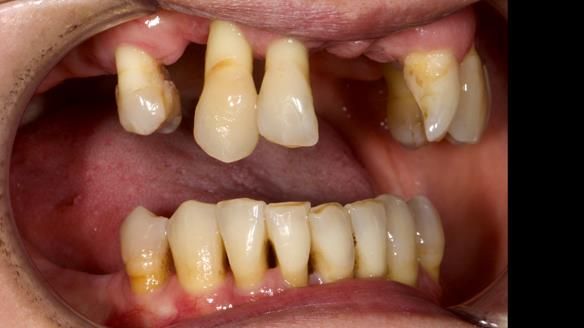

We provided her with an immediate upper denture (Mk 1), followed by a definitive metal-based upper denture (Mk 2). A lower removable partial denture was discussed, to be made only if needed once the upper treatment was complete. However, at review, this wasn’t necessary — Adnana had excellent neuromuscular control and function, even with a shortened dental arch (SDA).

Rowan, Sam Hesketh and Chris Hesketh provided the stunning technical work. I am very lucky to have them.